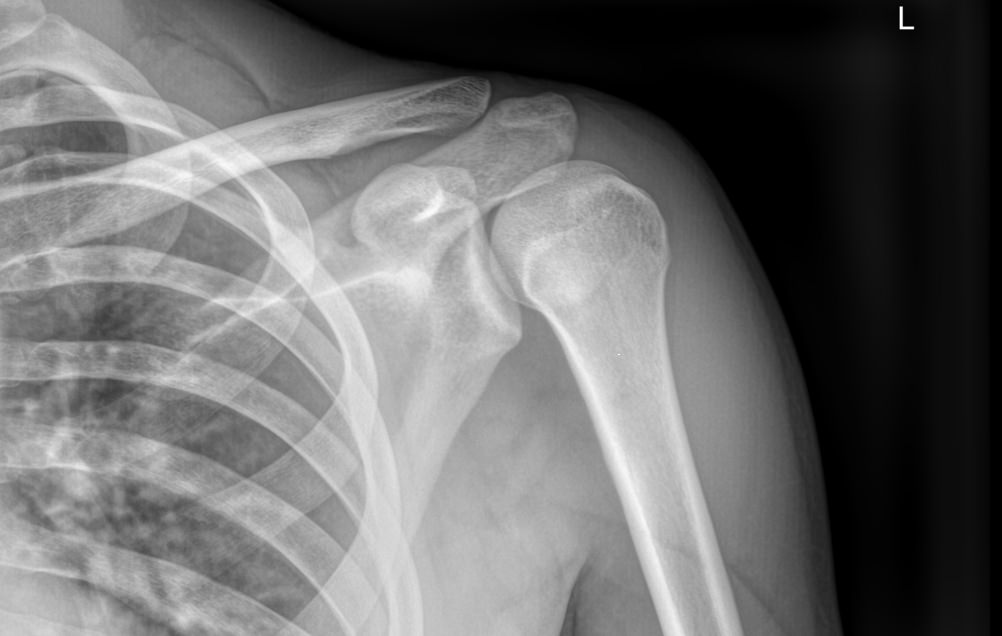

В случае травмы на снимке могут быть обнаружены:

• Отек мягких тканей;

• Расширение суставной щели;

• Ключица приподнята над акромионом;

• Перелом ключицы или клювовидного отростка лопатки;

• Изменения, свойственные дегенеративным процессам костной ткани.